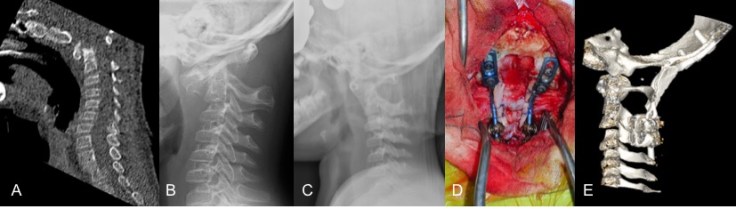

ossiculum terminale chez un enfant trisomique avec instabilité révélé par trauma mineur ; A, B : imagerie à l’admission ; C : contrôle après mise en traction : excellente réduction confiant la grande instabilité ; D, E : arthrodèse occipito-cervicale avec greffe par prélèvement de voûte occipitale -

-

réduction et consolidation après arthrodèse postérieure maintenir une immobilisation par minerve ou halo jusqu’à consolidation osseuse ; les trisomique ont souvent une ostéoporose qui compromet la consolidation.les techniques de fusion cranio-cervicales sont détaillées sur la page fusion crânio-cervicale